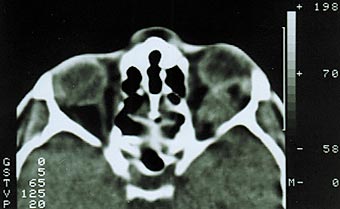

Менингиома второго типа роста диагностирована у 59% наших больных. Характеризуется прорастанием твердой мозговой оболочки и инфильтрацией экстраокулярных мышц, мягких тканей орбиты [1,6]. Как правило, в начале своего роста опухоль имеет эксцентричное расположение, смещая ствол зрительного нерва (рис. 3). В подобных случаях чрезвычайно трудно дифференцировать эксцентрично растущую менингиому от параневрально расположенной опухоли другого генеза, особенно при отсутствии изменений зрительных функций. Большая часть больных рано предъявляют жалобы на боли в орбите и одноименной половине головы. На глазном дне диагностируют застойный диск зрительного нерва. При длительном анамнезе (до нескольких лет) у трети больных на фоне застойного диска возникают кровоизлияния, развиваются оптико–цилиарные шунты для компенсации вызванного опухолью резкого затруднения оттока венозной крови на уровне решетчатой пластинки [10,11,19]. Зрительные функции сохраняются на высоком уровне несколько лет. Экзофтальм выражен в большей степени и достигает 8–14 мм, может быть осевым или со смещением, сочетается с невоспалительным отеком периорбитальных тканей и красным хемозом (рис. 4). Ограничение подвижности глаза следует расценивать, как симптом прорастания опухолью одной или нескольких экстраокулярных мышц. Чем ближе к вершине орбиты начинается рост опухоли, тем раньше появляется ограничение функций экстраокулярных мышц. Характерным для менингиомы зрительного нерва является отсутствие гиперостоза костей, столь свойственное внутричерепным менингиомам.

Рис. 3. Компьютерная томограмма больного с эксцентричным ростом менингиомы зрительного нерва.